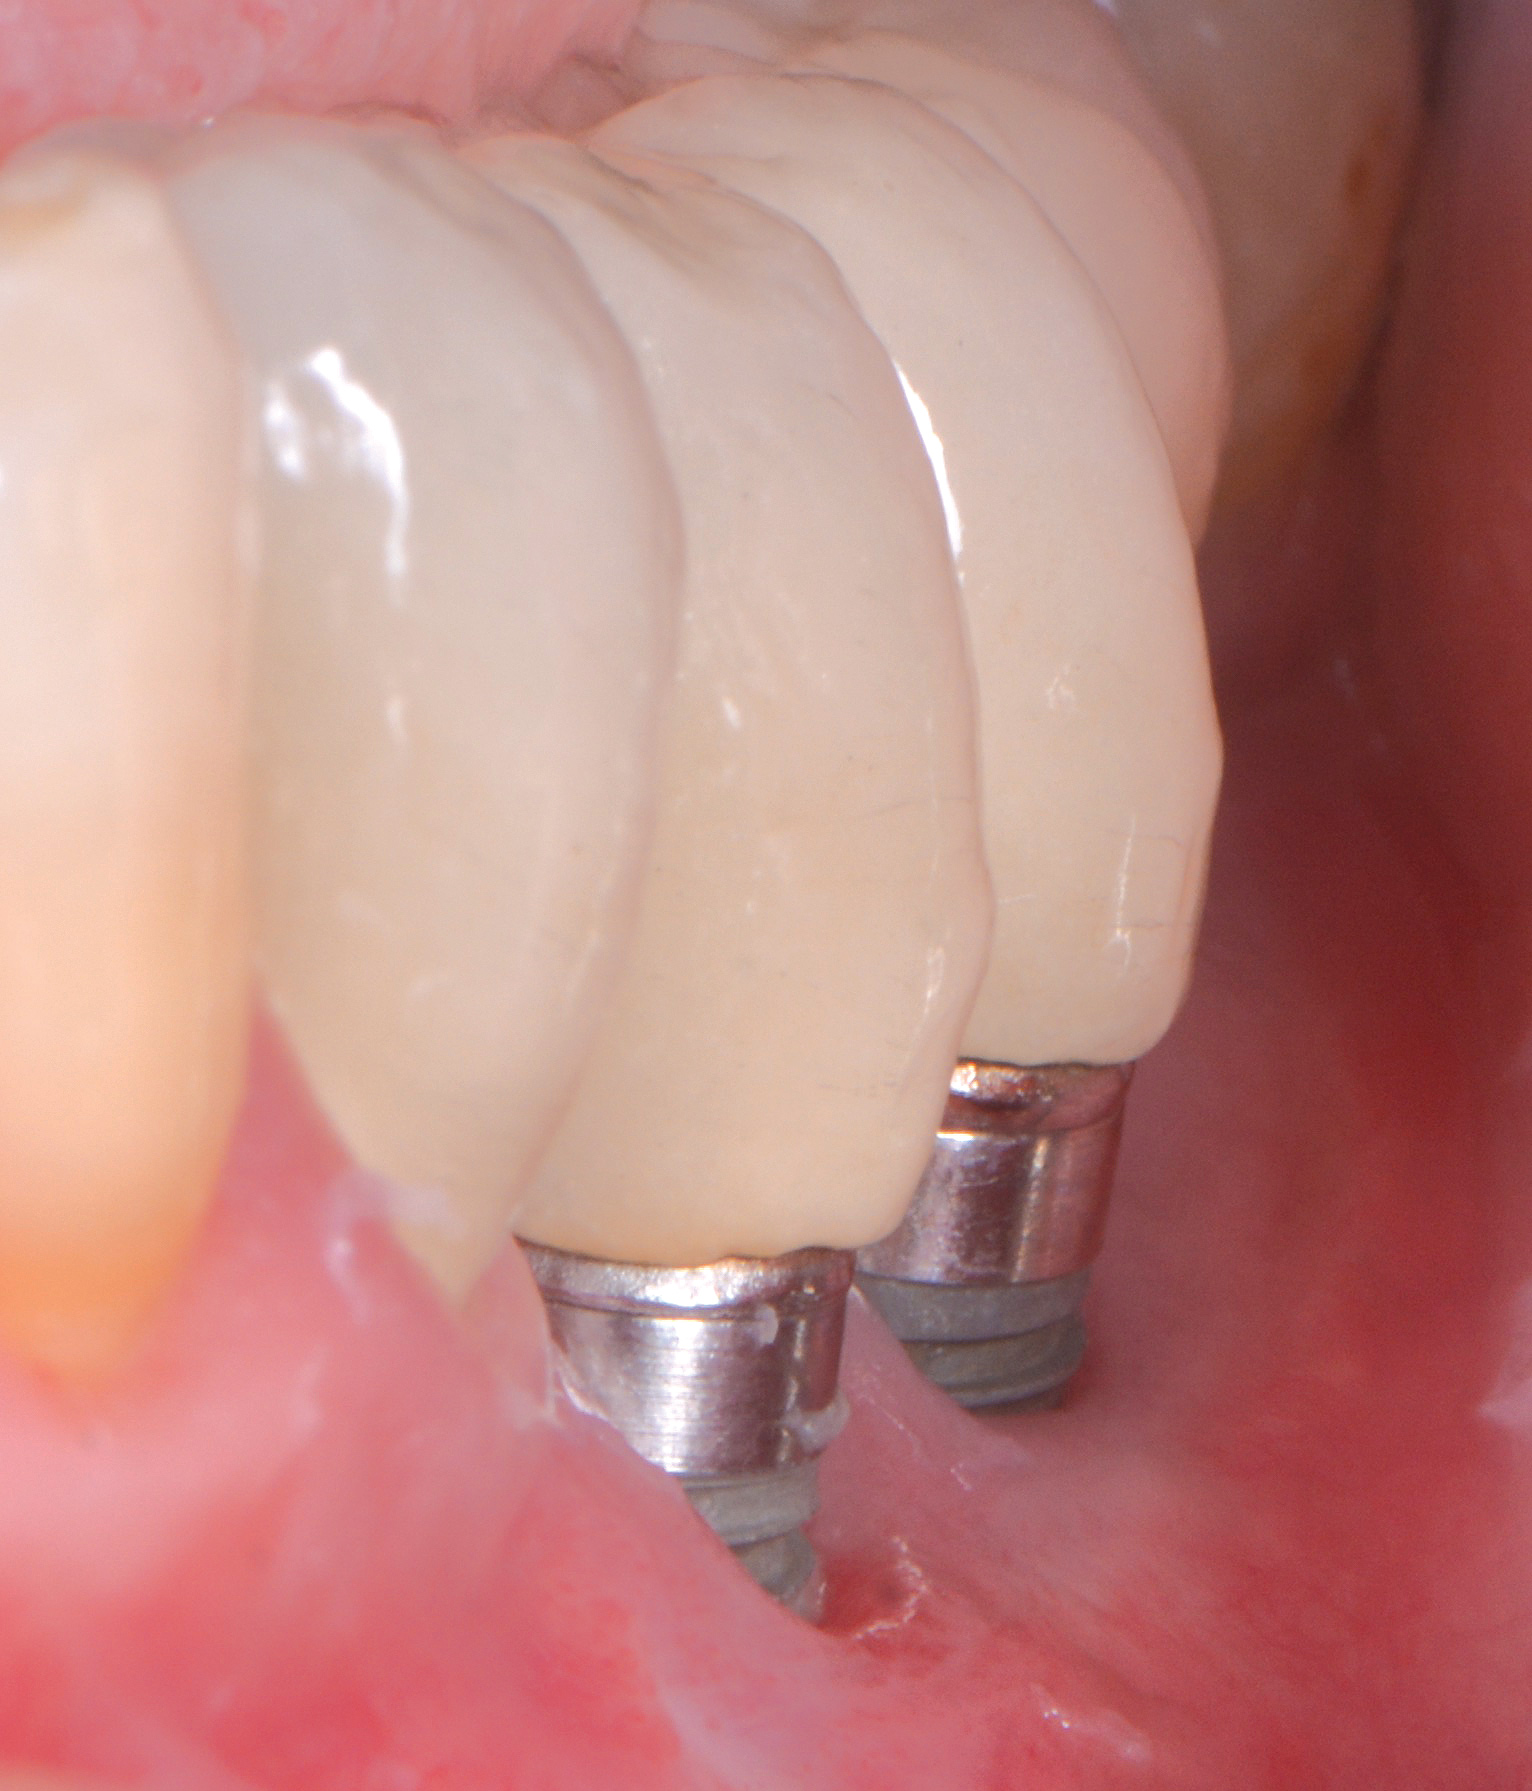

Fig 5. Clinical view of implants depicting suggested bone loss. Plaque was present throughout, and the distal-most implant had substantial purulent exudate.

Figure 5

Fig 6. From a more anterior view, it was apparent that the labial positioning of these implants was outside the alveolar housing.

Figure 6

Fig 7. Radiographic image of the area suggesting severe bone loss around the dental implants.

Figure 7